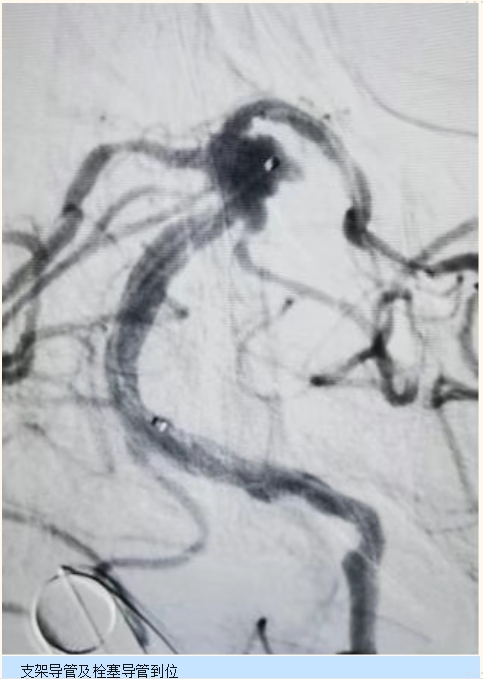

时间就是生命!院前医生争分夺秒,同步联系神经外科团队,迅速启动 “绿色通道”,并通知手术室做好术前准备。朱大娘抵达急诊后,各项术前工作高效完成,随即被直接送入手术室。手术中,DSA 清晰显示基底动脉存在不规则动脉瘤,经过精准的 3D 测量,医生成功置入支架及栓塞导管,实现动脉瘤完全闭塞。术后,朱大娘转入 NICU 接受镇痛、镇静及降颅压治疗。仅仅一天后,朱大娘便清醒过来,还能自主活动,生命体征平稳,成功从死神手中夺回生机。